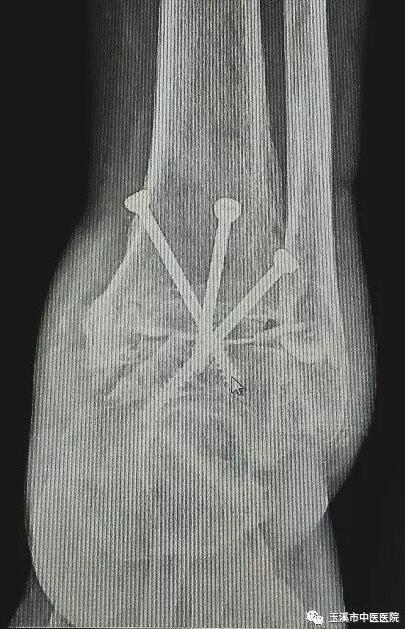

在醫(yī)務(wù)人員緊張的情況下,骨傷Ⅰ科克服種種困難,先后派出3名一線醫(yī)務(wù)人員赴千里之外的德欽縣人民醫(yī)院進(jìn)行對(duì)口援助。朱金富醫(yī)生是今年8月份去到藏區(qū)的,一到那里便積極投入工作。一位五十六歲藏族阿媽來到醫(yī)院看病時(shí),左踝關(guān)節(jié)疼痛、畸形三十余年了。 朱醫(yī)生將她收治入院,在相關(guān)檢查后,為她做了左踝關(guān)節(jié)融合術(shù)。術(shù)后藏族阿媽左踝關(guān)節(jié)功能明顯改善,生活及勞動(dòng)能力有所恢復(fù),一家人皆大歡喜。

術(shù)后X光片(左踝關(guān)節(jié)側(cè)位)